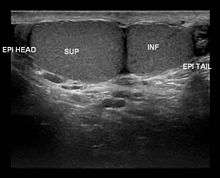

Polyorchidism is generally diagnosed via an ultrasound examination of the testicles. However, the diagnosis of polyorchidism should include histological confirmation. The most common form is triorchidism, or tritestes, where three testicles are present. The condition is usually asymptomatic. A man who has polyorchidism is known as a polyorchid.